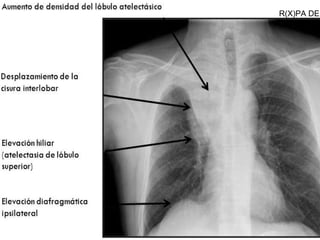

Signos directos

 Desplazamiento cisural, cuando la atelectasia

es lobar, las cisuras se retraen hacia el lugar

afectado.

 Pérdida de la aireación, que se observa como

una imagen radiopaca en el lugar afectado.

 Signos broncovasculares, debido a la

retracción pulmonar hay apelotonamiento de

vasos al nivel de la lesión.

Signos indirectos

 Diafragma, elevado en el lado de la lesión.

 Tráquea, Hilio y Mediastino desviados hacia

el lado de la lesión.

 Espacio intercostal, disminuido debido a

que la trayectoria de las costillas, sobre

todo en el extremo anterior, se hace más

oblicua.

 Enfisema compensador, debido a que el

área adyacente o el pulmón contrario sufre

hiperinsuflación

R(X)PA DE

TORAX